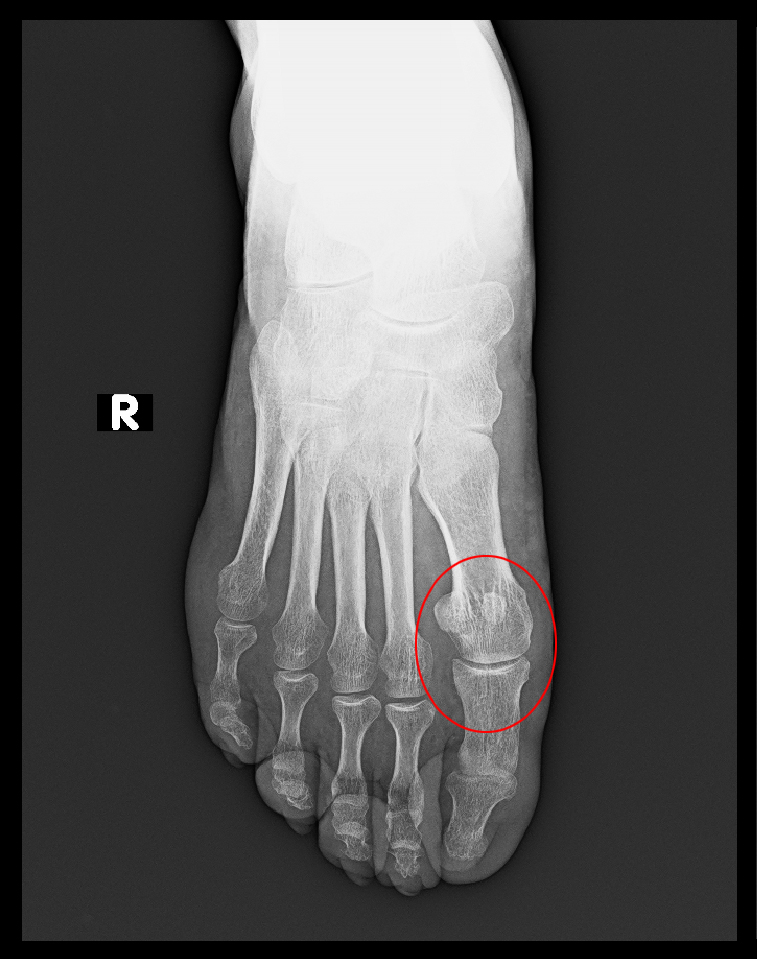

3年間服薬を継続して、令和4年4月12日以後患者さんの判断で服薬を中止されています。

56才男 Xp2.jpg

1年8か月後の令和5年12月2日(56才時)に右第1趾MP関節痛で受診され、痛風疑いで採血するも、尿酸値は4.0で正常、RF217、抗CCP抗体175と異常が悪化していて、リウマチの可能性を否定できるわけではないのですが、他にはリウマチの症状はなく右第1趾痛は服薬で12月5日には消失し、以後7年11月まで特に受診はありません。リウマチの症状は治癒していると受け止められます。血液検査が異常値であってもリウマチの服薬が必要とは限らず、この患者さんは単周期型のリウマチであったのであろうと理解します。